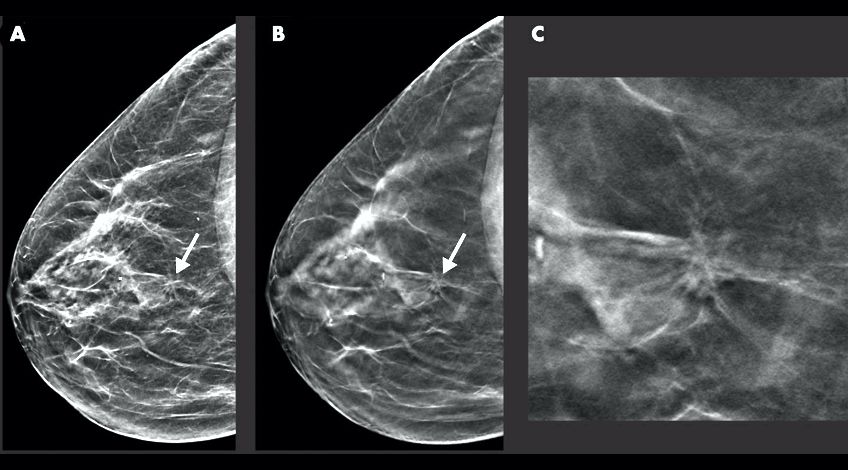

La Organización Mundial de la Salud (OMS) recomiendan realizar una mamografía de diagnóstico de forma regular para detectar el cáncer o cualquier anomalía de manera oportuna. En Chile una de las causas de muerte más frecuentes entre las mujeres es el cáncer de mama.